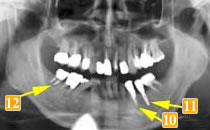

56歳男性

インプラント治療の必要性を自覚して他の歯科医院より依頼されたケースです。

初診時、左下一番奥の歯(レントゲンでは右下

)は骨が吸収してしまっています。

この状態で手前の歯と連結して長期間経過したため、より骨が無くなってしまいました。

骨が少なすぎてインプラントを打つ厚みがありません。この時点では手術はできませんと説明しました。

この歯を抜歯した際に骨移植を行いました。あまりに骨が少なかったのでインプラントを打てる厚みまで回復するのに2年の経過観察をしました。

-

先に右で噛めるようにインプラントにて治療を行い、

骨移植し骨ができたところでインプラント植立を行いました。右下奥のブリッジ(レントゲンでは

)は、ブリッジが長かったためか、親知らずが溶けてしまっています。負担の大きい手前の2本の小臼歯も揺れていました。

手術した結果、インプラントで噛むことができて、手前の歯の骨が安定しました。

このように、インプラントは他の歯を長持ちさせる為にも有効な方法です。